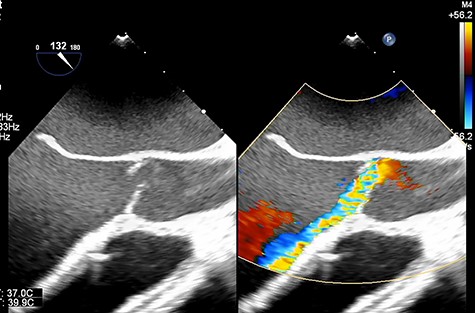

A 33-year-old man with familial dilated cardiomyopathy was urgently admitted to our hospital due to acute decompensation of heart failure with brain natriuretic peptide of 1124.5 pg/ml. Transthoracic echocardiography (TEE) showed left ventricular diastolic diameter of 75 mm, left ventricular systolic diameter of 71 mm, left ventricular ejection fraction of 20% with diffuse hypokinesis. Despite intensive medical treatment with dobutamine at 4 mcg/kg/min, his hemodynamic status did not improve: blood pressure (BP) of 91/56 (67) mm Hg, pulmonary artery pressure (PAP) of 56/18(34) mm Hg, pulmonary capillary wedge pressure of 36 mm Hg, central venous pressure (CVP) of 16 mm Hg. An Impella 5.0 catheter was emergently implanted via the right femoral artery as bridging therapy. After the initiation of Impella at the maximum flow rate, TEE showed no AI. The patient’s hemodynamic status stabilized with dopamine at 1.5 mcg/kg/min and dobutamine at 4.2 mcg/kg/min: BP of 79/66(70) mm Hg, PAP of 36/19(25) mm Hg, CVP of 9 mm Hg. Fifteen days after Impella insertion, heart transplantation was approved. HeartMate III (Abbott, Plymouth, MN, USA) implantation was performed. Intraoperative TEE detected mild AI before the Impella device was removed, which worsened to moderate AI after removal due to prolapse of noncoronary cusps (Fig. 1). At that time, BP of 107/48(67) mm Hg, PAP of 68/33(48) mm Hg and CVP of 9 mm Hg. After Park’s stitch procedure (central AV closure) was performed, diastolic arterial BP increased, with BP of 86/60(70) mm Hg, PAP of 41/25(30) mm Hg and CVP of 12 mm Hg. However, on postoperative Day 1, TEE showed the coaptation stitch on the right and noncoronary cusps had failed, causing severe AI (Fig. 2A and B). In addition, BP decreased to 84/42(49) mm Hg. Consequently, emergent AV replacement was performed. Five days after AV replacement, the patient was discharged from the intensive care unit without any complications.

Transesophageal echocardiography showing moderate aortic insufficiency (AI) due to prolapse of noncoronary cusps after Impella removal.